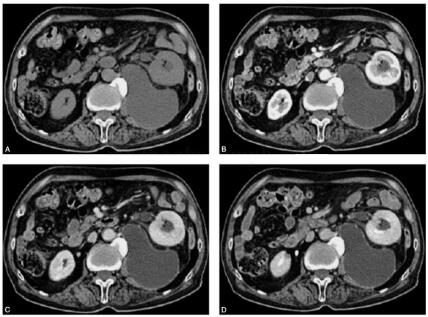

患者男,80岁,以“左腰疼痛20天”为主诉门诊检查(图1)。

图1 左肾后方见不规则囊性密度病灶,壁薄,其内呈液体密度,囊壁明显强化,内部未见强化,左肾后间隙延伸至髂腰肌下缘水平,其前上缘局部可见尖角状改变,与相邻左输尿管关系密切,邻近腰大肌受压萎缩,左髂肌受压。右输尿管未见异常。F图示左输尿管上段内见类椭圆形高密度结石影,其近端输尿管及左肾盂轻度扩张,左肾增大前移,肾周脂肪间隙见少许渗出絮状影